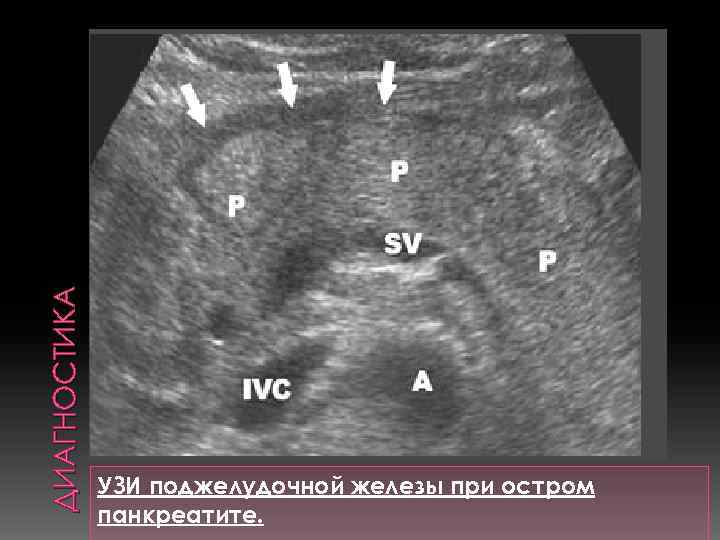

ДИАГНОСТИКА УЗИ поджелудочной железы при остром панкреатите.

ДИАГНОСТИКА УЗИ поджелудочной железы при остром панкреатите.